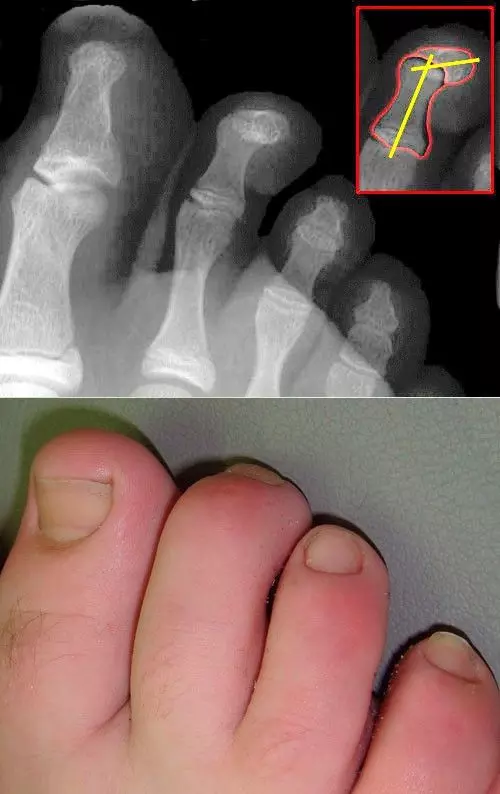

Mallet Toe is flexion at the distal interphalangeal joint (DIPJ), and Hammer Toe is flexion at the proximal interphalangeal joint (PIPJ). Both of these conditions are most common in the second toe. They are caused by ill-fitting shoes or pressure from the adjacent first toe having Hallux Valgus (lateral deviation of the Hallux). The change in shape of the toe can cause shoes to rub against it and this can lead to painful corns or calluses.

Image - X-ray and Physical Appearance of Mallet Toe

Creative commons source by J. Lengerke [CC BY-SA 3.0 de (https://creativecommons.org/licenses/by-sa/3.0/de/deed.en)]